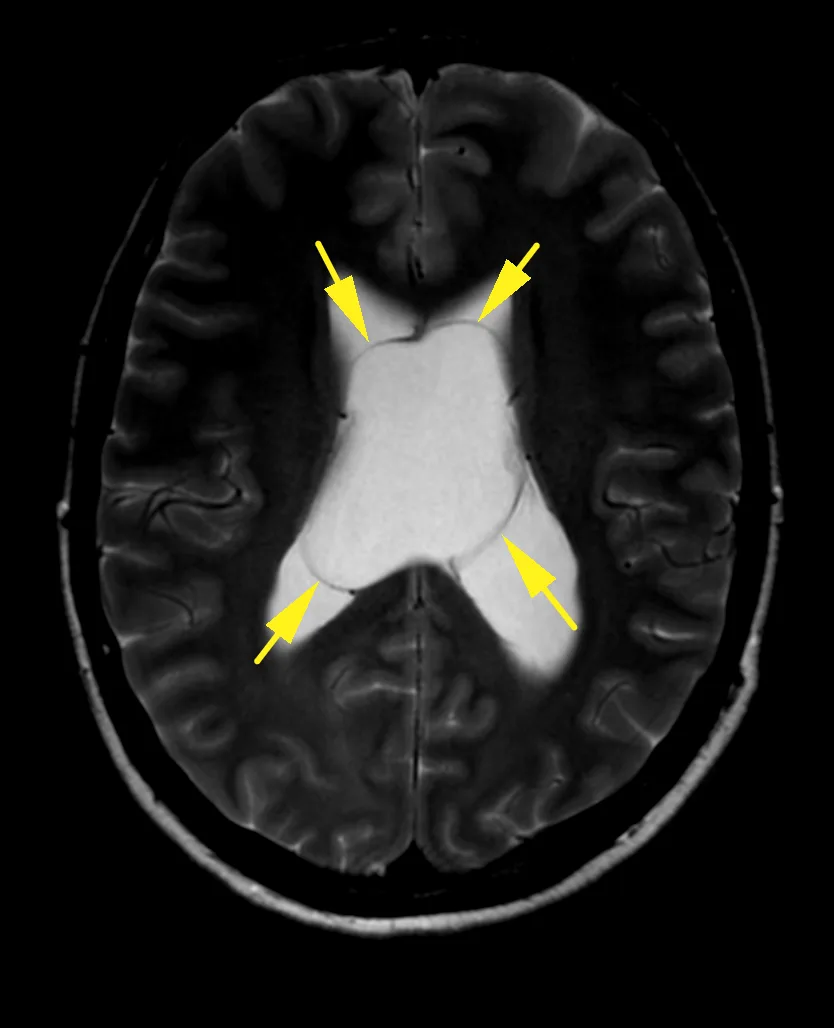

Наконец-то я увидел это воочию! Киста полости Верги, промежуточного паруса, осложнённая гидроцефалией. Из анамнеза: Низкое артериальнео давление, нарушение речи, затуманенное сознание, головная боль, головокружение, в 1989 году перенёс менингит.

А Вы видали такое? Я впервые вижу, раньше только читал в литературе.